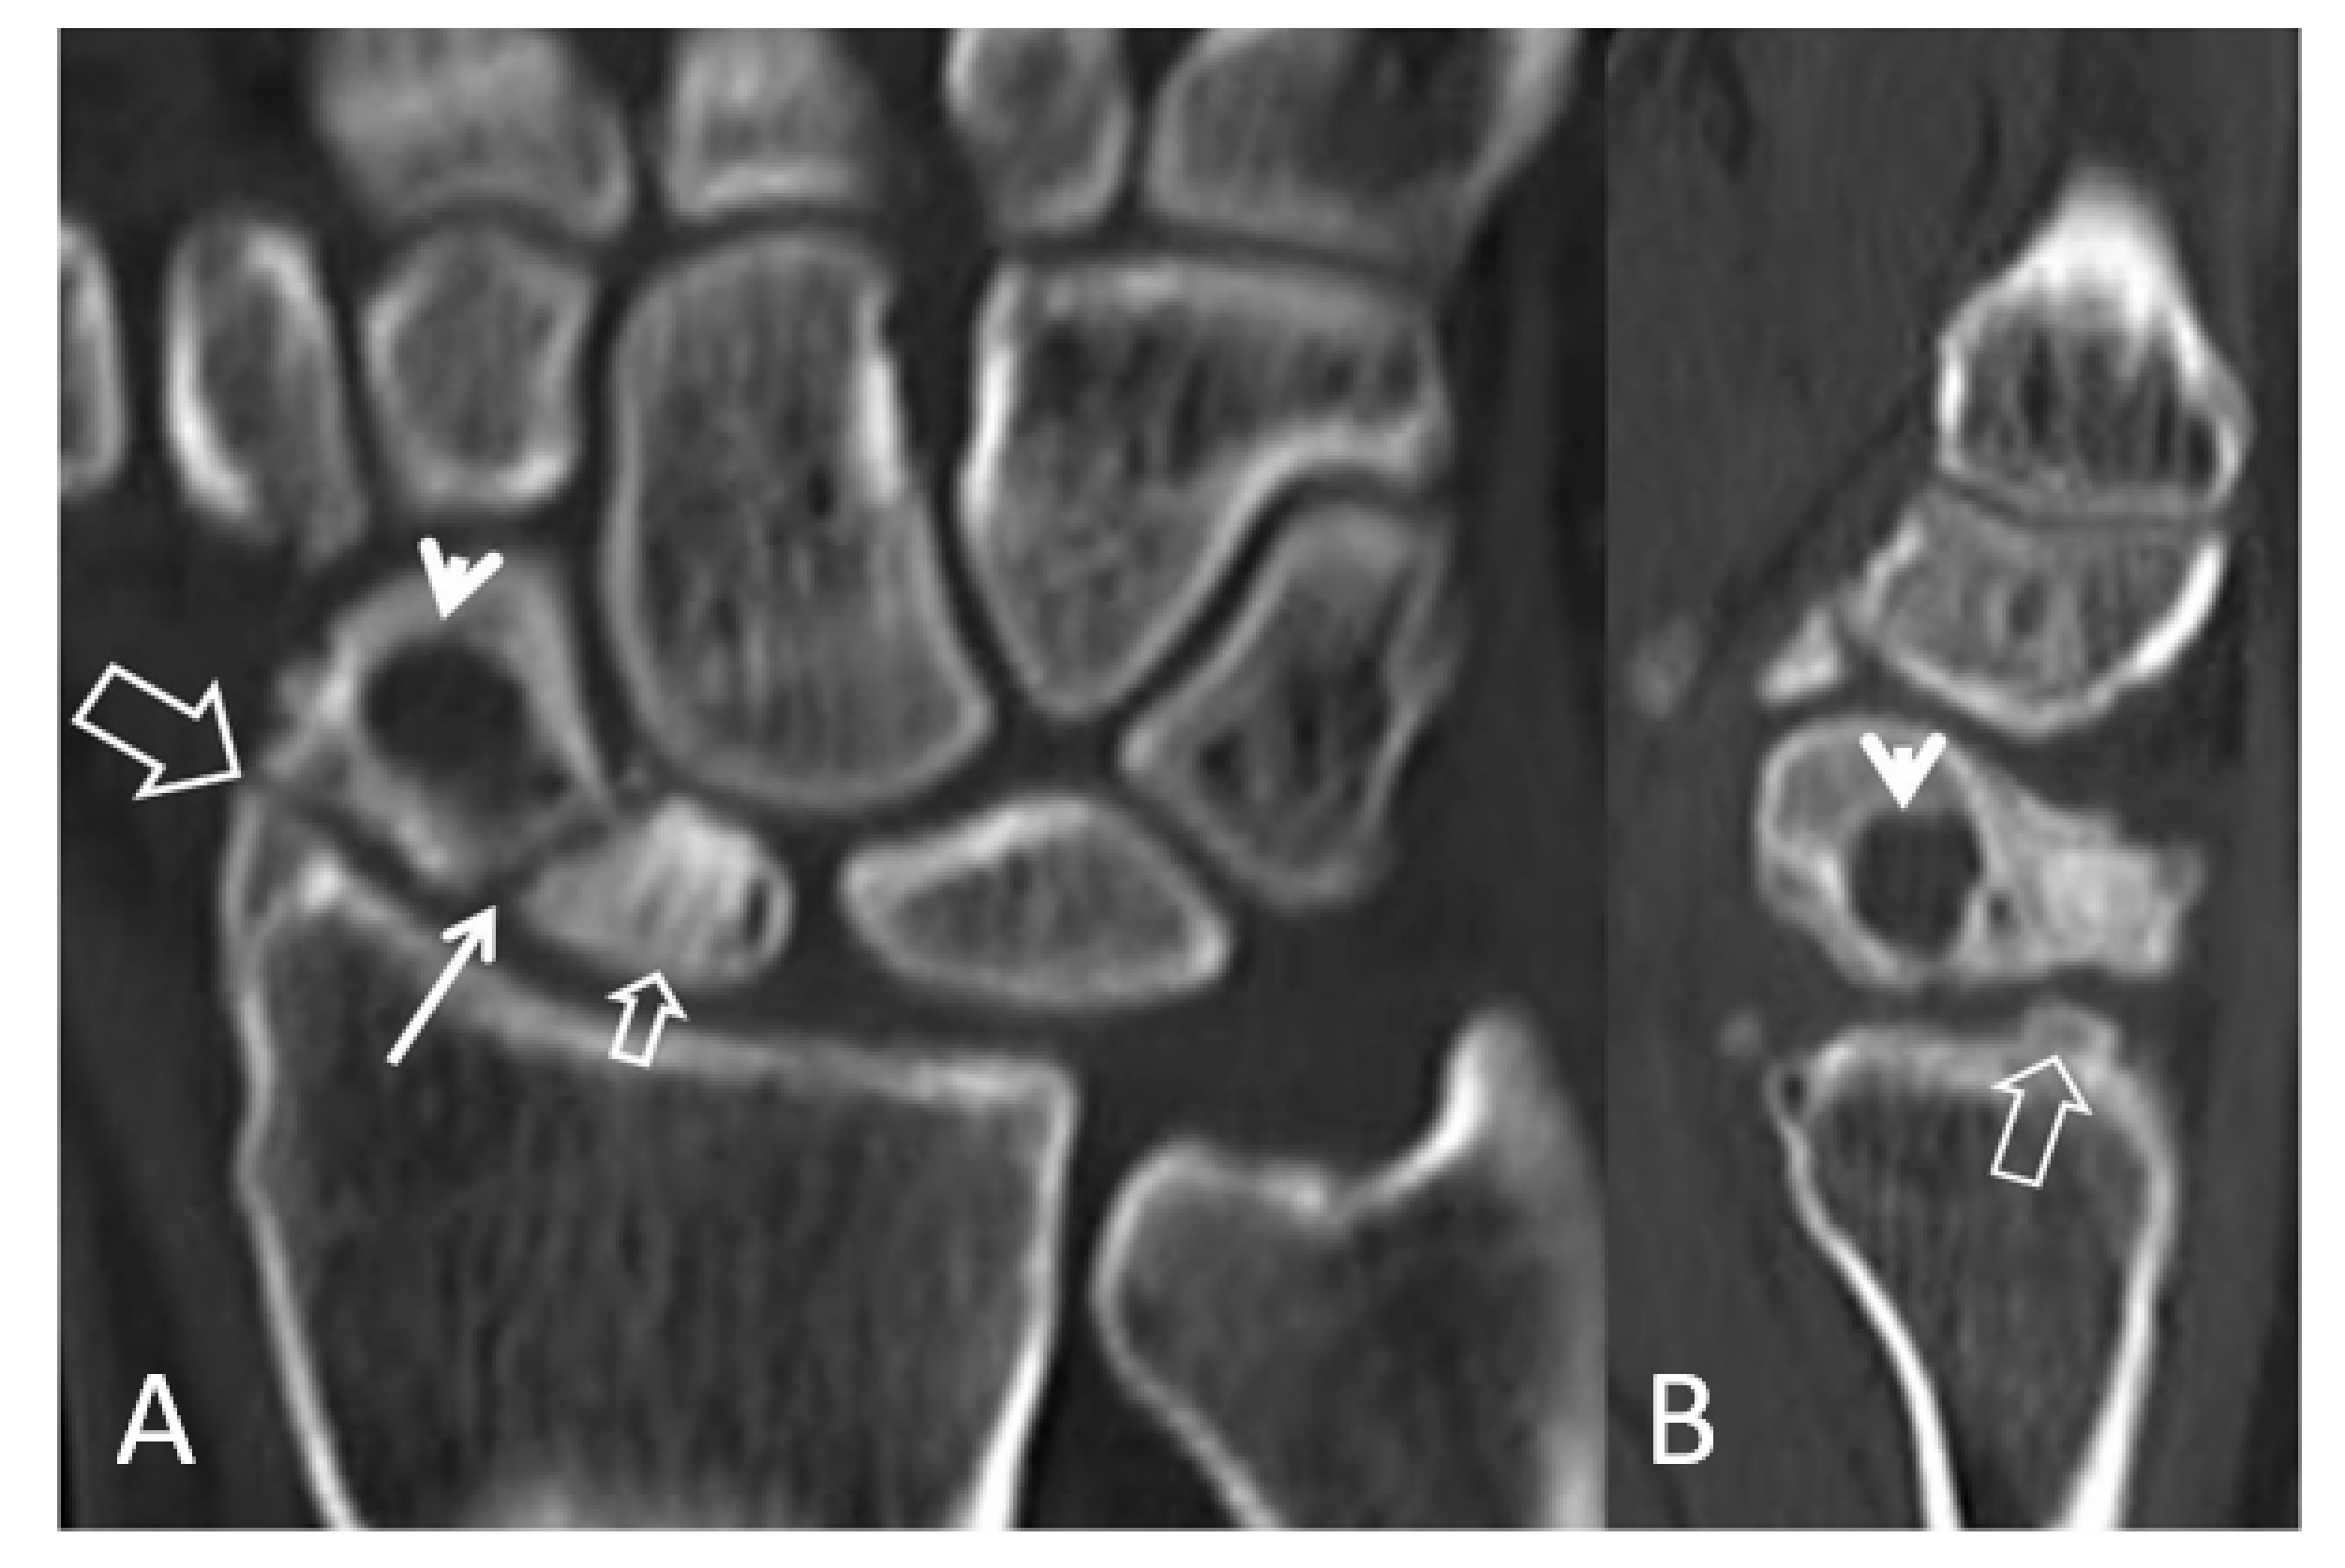

Multidetector computed tomography (MDCT) is a valuable tool in evaluating the wrist’s joint spaces, because of its high spatial resolution and the absence of overlapping tissues. Plain MDCT images may show the early degenerative findings, including subchondral bone sclerosis with or without cyst formation (Figure 5, Figure 6 and Figure 7).

Figure 6.

Coronal (A) and sagittal (B) CT reconstructions of a 23-year-old male patient with an injury 7 years prior to current imaging. SNAC wrist is shown with radioscaphoid joint space narrowing with osteophyte formation (large open arrow left, open arrow right), secondary to proximal pole osteonecrosis (small open arrow left) and pseudarthrosis (thin arrow left). Large cyst formation is shown in the distal pole of the scaphoid (arrowheads).